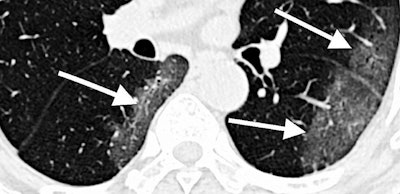

CT scan of lungs of COVID-19 patient with areas described by radiologists as resembling grains of ground glass. Image courtesy of RSNA.The goal of the center is to lead the development and implementation of new diagnostic tools, including machine-learning algorithms, that will enable the rapid and accurate assessment of disease status and help physicians optimize patient treatment.